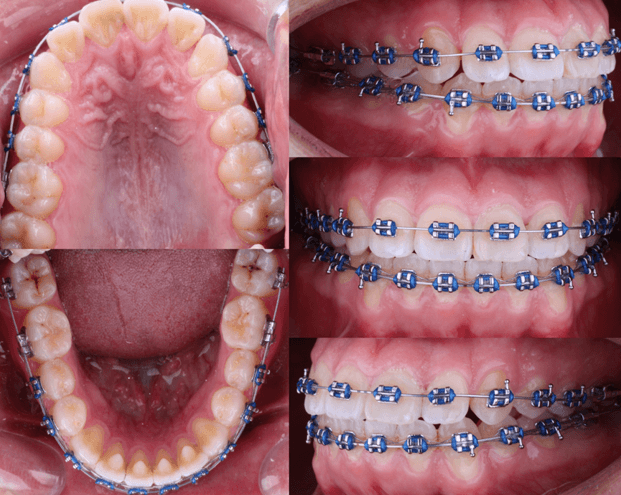

A la evaluacion intraoral presentaba deglusion atipica y una maloclusion molar clase III bilateral, clase II canina del lado derecho y clase III canina del lado izquierdo. Forma de arcada cuadrada en superior y ovoide en inferior. Biprotrusion dental. Presencia de OD 18, 28, 38, 48 erupcionados. Tremas de 3-3 en el maxilar inferior. Mordida cruzada anterior. Overjet de -1 mm. Overbite 0mm.

Fig 2. Fotografias intraorales